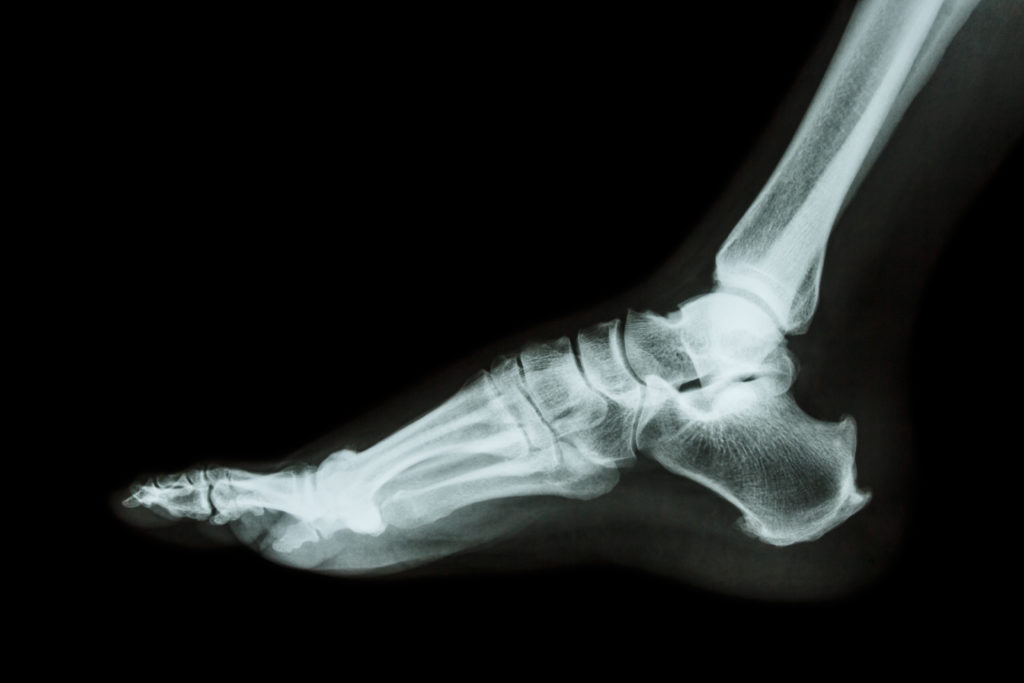

Is it plantar fasciitis, heel spurs, or something different? The hope of finding out exactly what’s going on beneath the surface encourages many people to seek out X-rays to determine the exact cause of heel or foot pain. After all, a Superman-style peek into the inner workings of your feet should reveal all, right?

While X-rays are a popular first line of defense when it comes to determining the cause of foot pain, they aren’t particularly helpful in diagnosing plantar fasciitis. Why? In large part because X-rays are much better at showing bones rather than soft tissue like muscles and ligaments. And since the main player in plantar fasciitis is a ligament–the fascia or arch of your foot–it’s difficult to determine the presence or extent of damage through an X-ray.

X-rays can detect the presence of heel spurs–sharp, protruding calcium deposits that may dig into the fatty pad of the heel, causing pain. However, the presence of heel spurs does not necessarily mean that someone has plantar fasciitis. While plantar fasciitis can cause the development of heel spurs as the body attempts to compensate for the damaged fascia, at other times heel spurs develop independently of plantar fasciitis and do not cause pain.

While X-rays aren’t particularly good for diagnosing plantar fasciitis, they can rule out other causes of foot pain, including stress fractures, cysts, and other problems related to the bones of the foot and ankle.